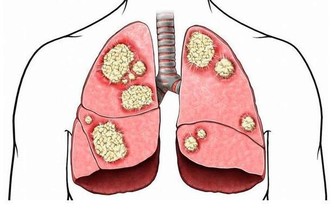

腎臟好比是身體的“淨水機”,每天過濾和清潔200升血液,

把有用的東西留在血液中,讓代謝的廢物排出體外。

同時,腎臟也被稱為“工廠”,它生產了很多與人體內分泌、代謝有關的激素,

幫助調節血壓、維持骨骼功能、生成紅細胞。

別看腎臟功能強大,卻是一個脆弱的器官。

調查顯示,我國慢性腎病的發病率逐年上升,城市中每10人就有一例,

因此,我們應該時刻關注腎臟健康,留意它發出的“維修”信號。